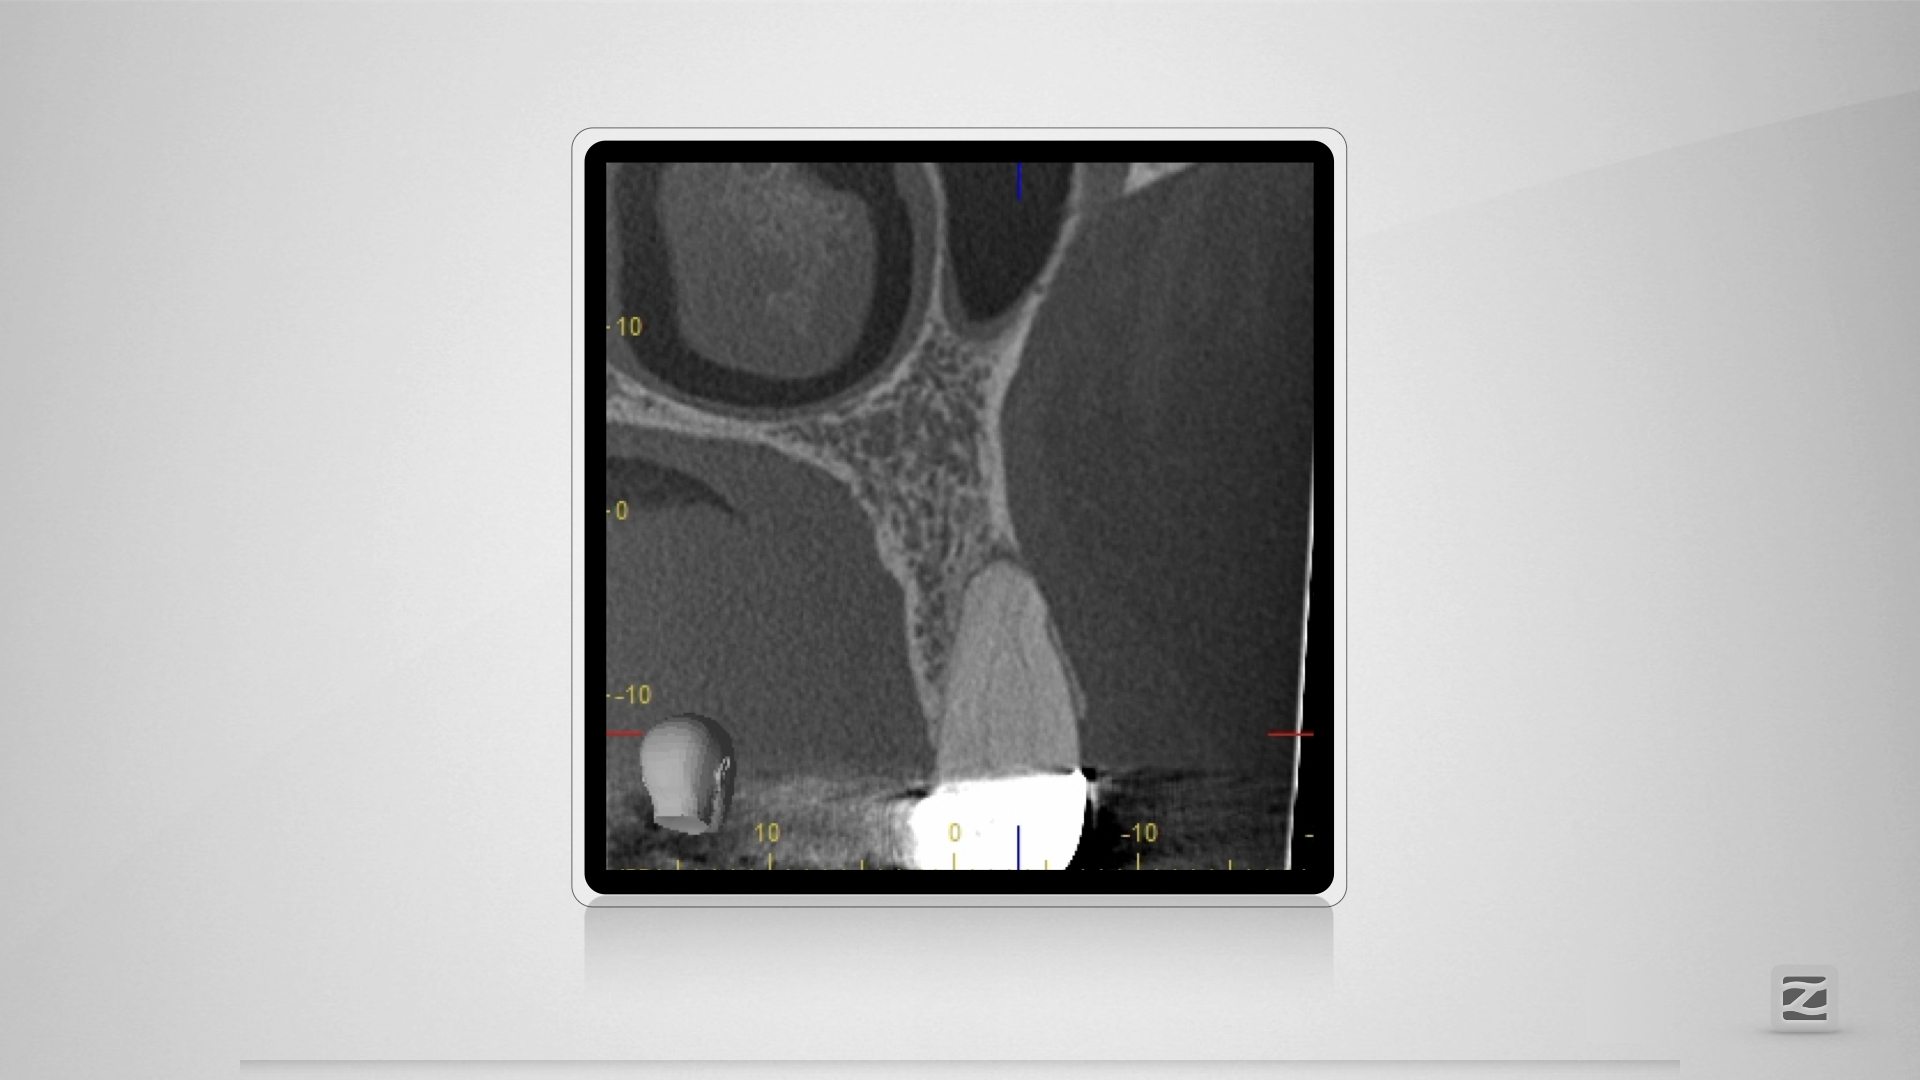

14D.003

H mit kleiner Tücke